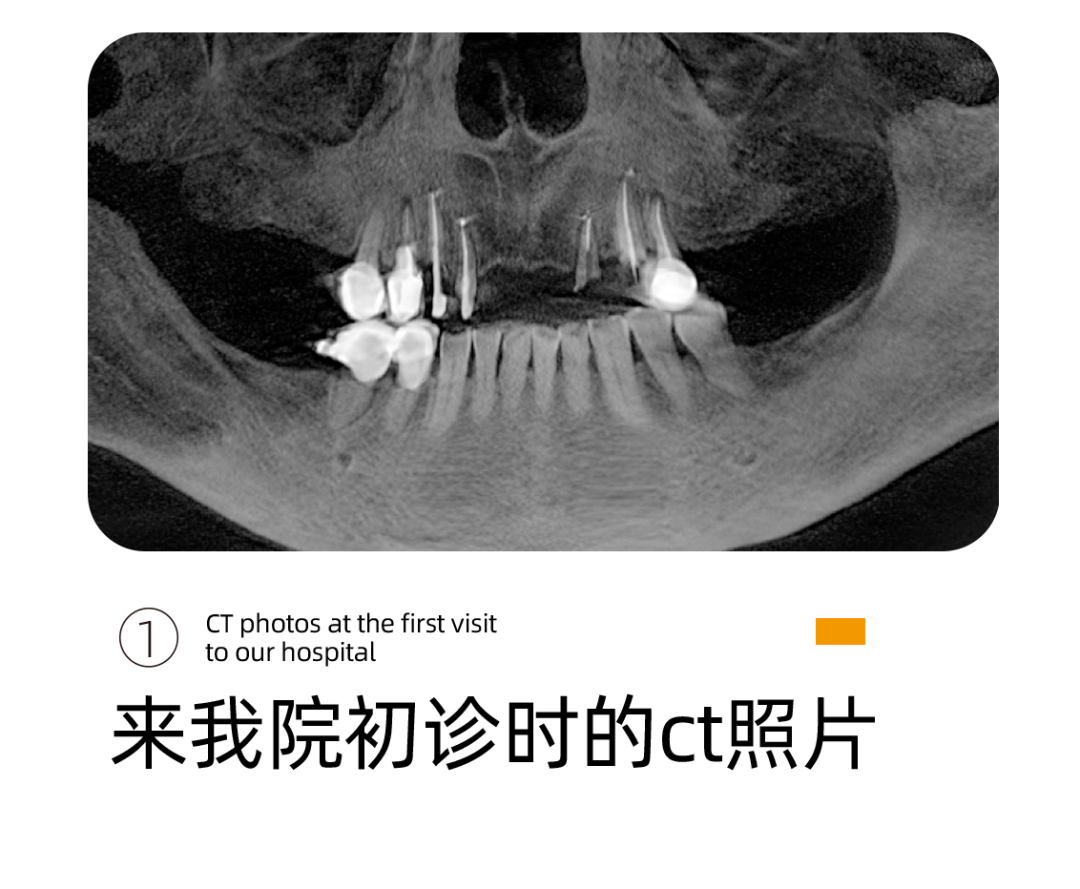

这是阿姨来找李雪松院长看牙最开始的样子。

不是这样的图片,我们都没有办法理解这样的口腔情况对一个老人来说意味着什么。阿姨说的吃东西靠吞不是被夸大的感受,而是她每天的日常。